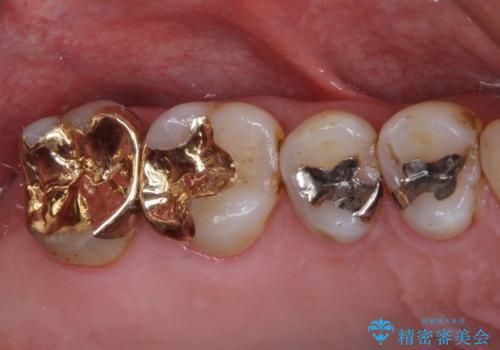

- アンバランスな色や形、歯肉ラインの黒い縁が目立ってしまったブリッジの作り直しを希望して来院された患者様です。

自然な仕上がりとするため、金属を使用しないオールセラミックブリッジにより補綴治療を行うこととしました。